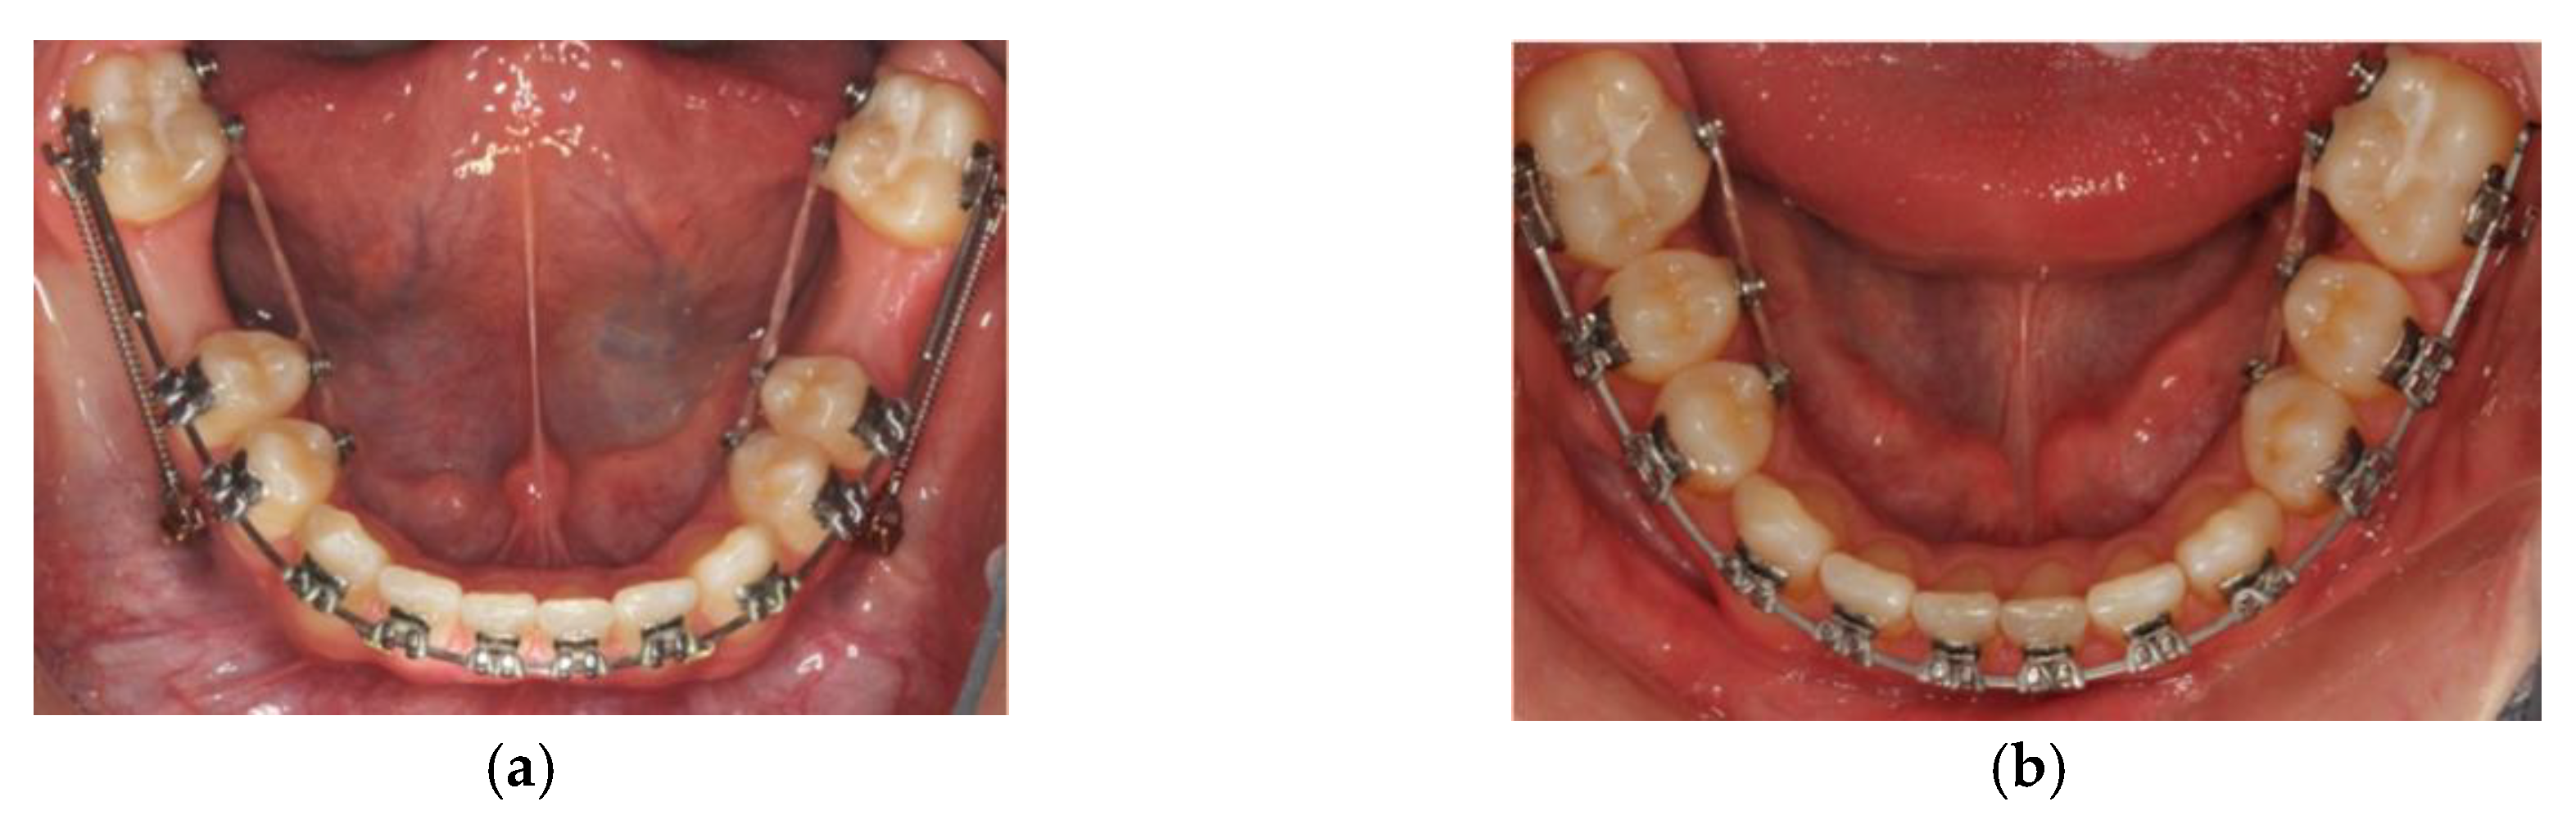

2.2. Case 2—Timely Extraction of FPMs

Discussion

- ▪

- Round tipping of upper and lower second permanent molars;

- Distal tipping of lower second premolars;

- Spacing in the lower arch;

- Excessive retroclination of the lower labial segment that worsened an inherent deepbite.